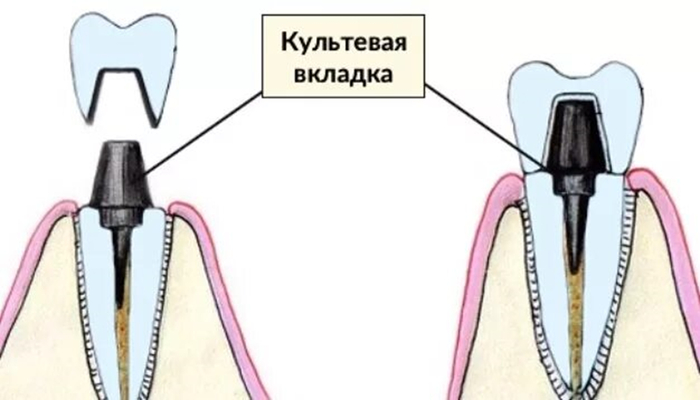

Изготавливают по слепку в зуботехнической лаборатории. Представлены чаще всего культевыми вкладками (они же ШКВ, ЛКВ), где штифт и культевая часть являются одним целым.

Формируется полость и путь введения под вкладку, один из каналов распломбировывается на 1\2-2\3 длины корня, снимается слепок и отдается зубному технику.